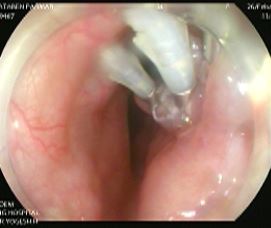

Doctors at Noble gastro hsopital performed two third space endoscopic surgeries back to back for Achalasia Cardia called per oral endoscopic myotomy a foodpipe motility disorder in which patient has inability to swallow food. This involves no external incision and entire surgery is performed per orally by endoscopy.

Per oral endoscopic myotomy performed at Noble Gastro Hospital for Achalasia cardia this is an endoscopic method for treating difficulty in swallowing food. Diagnosis of Achalasia is confirmed by manometry.